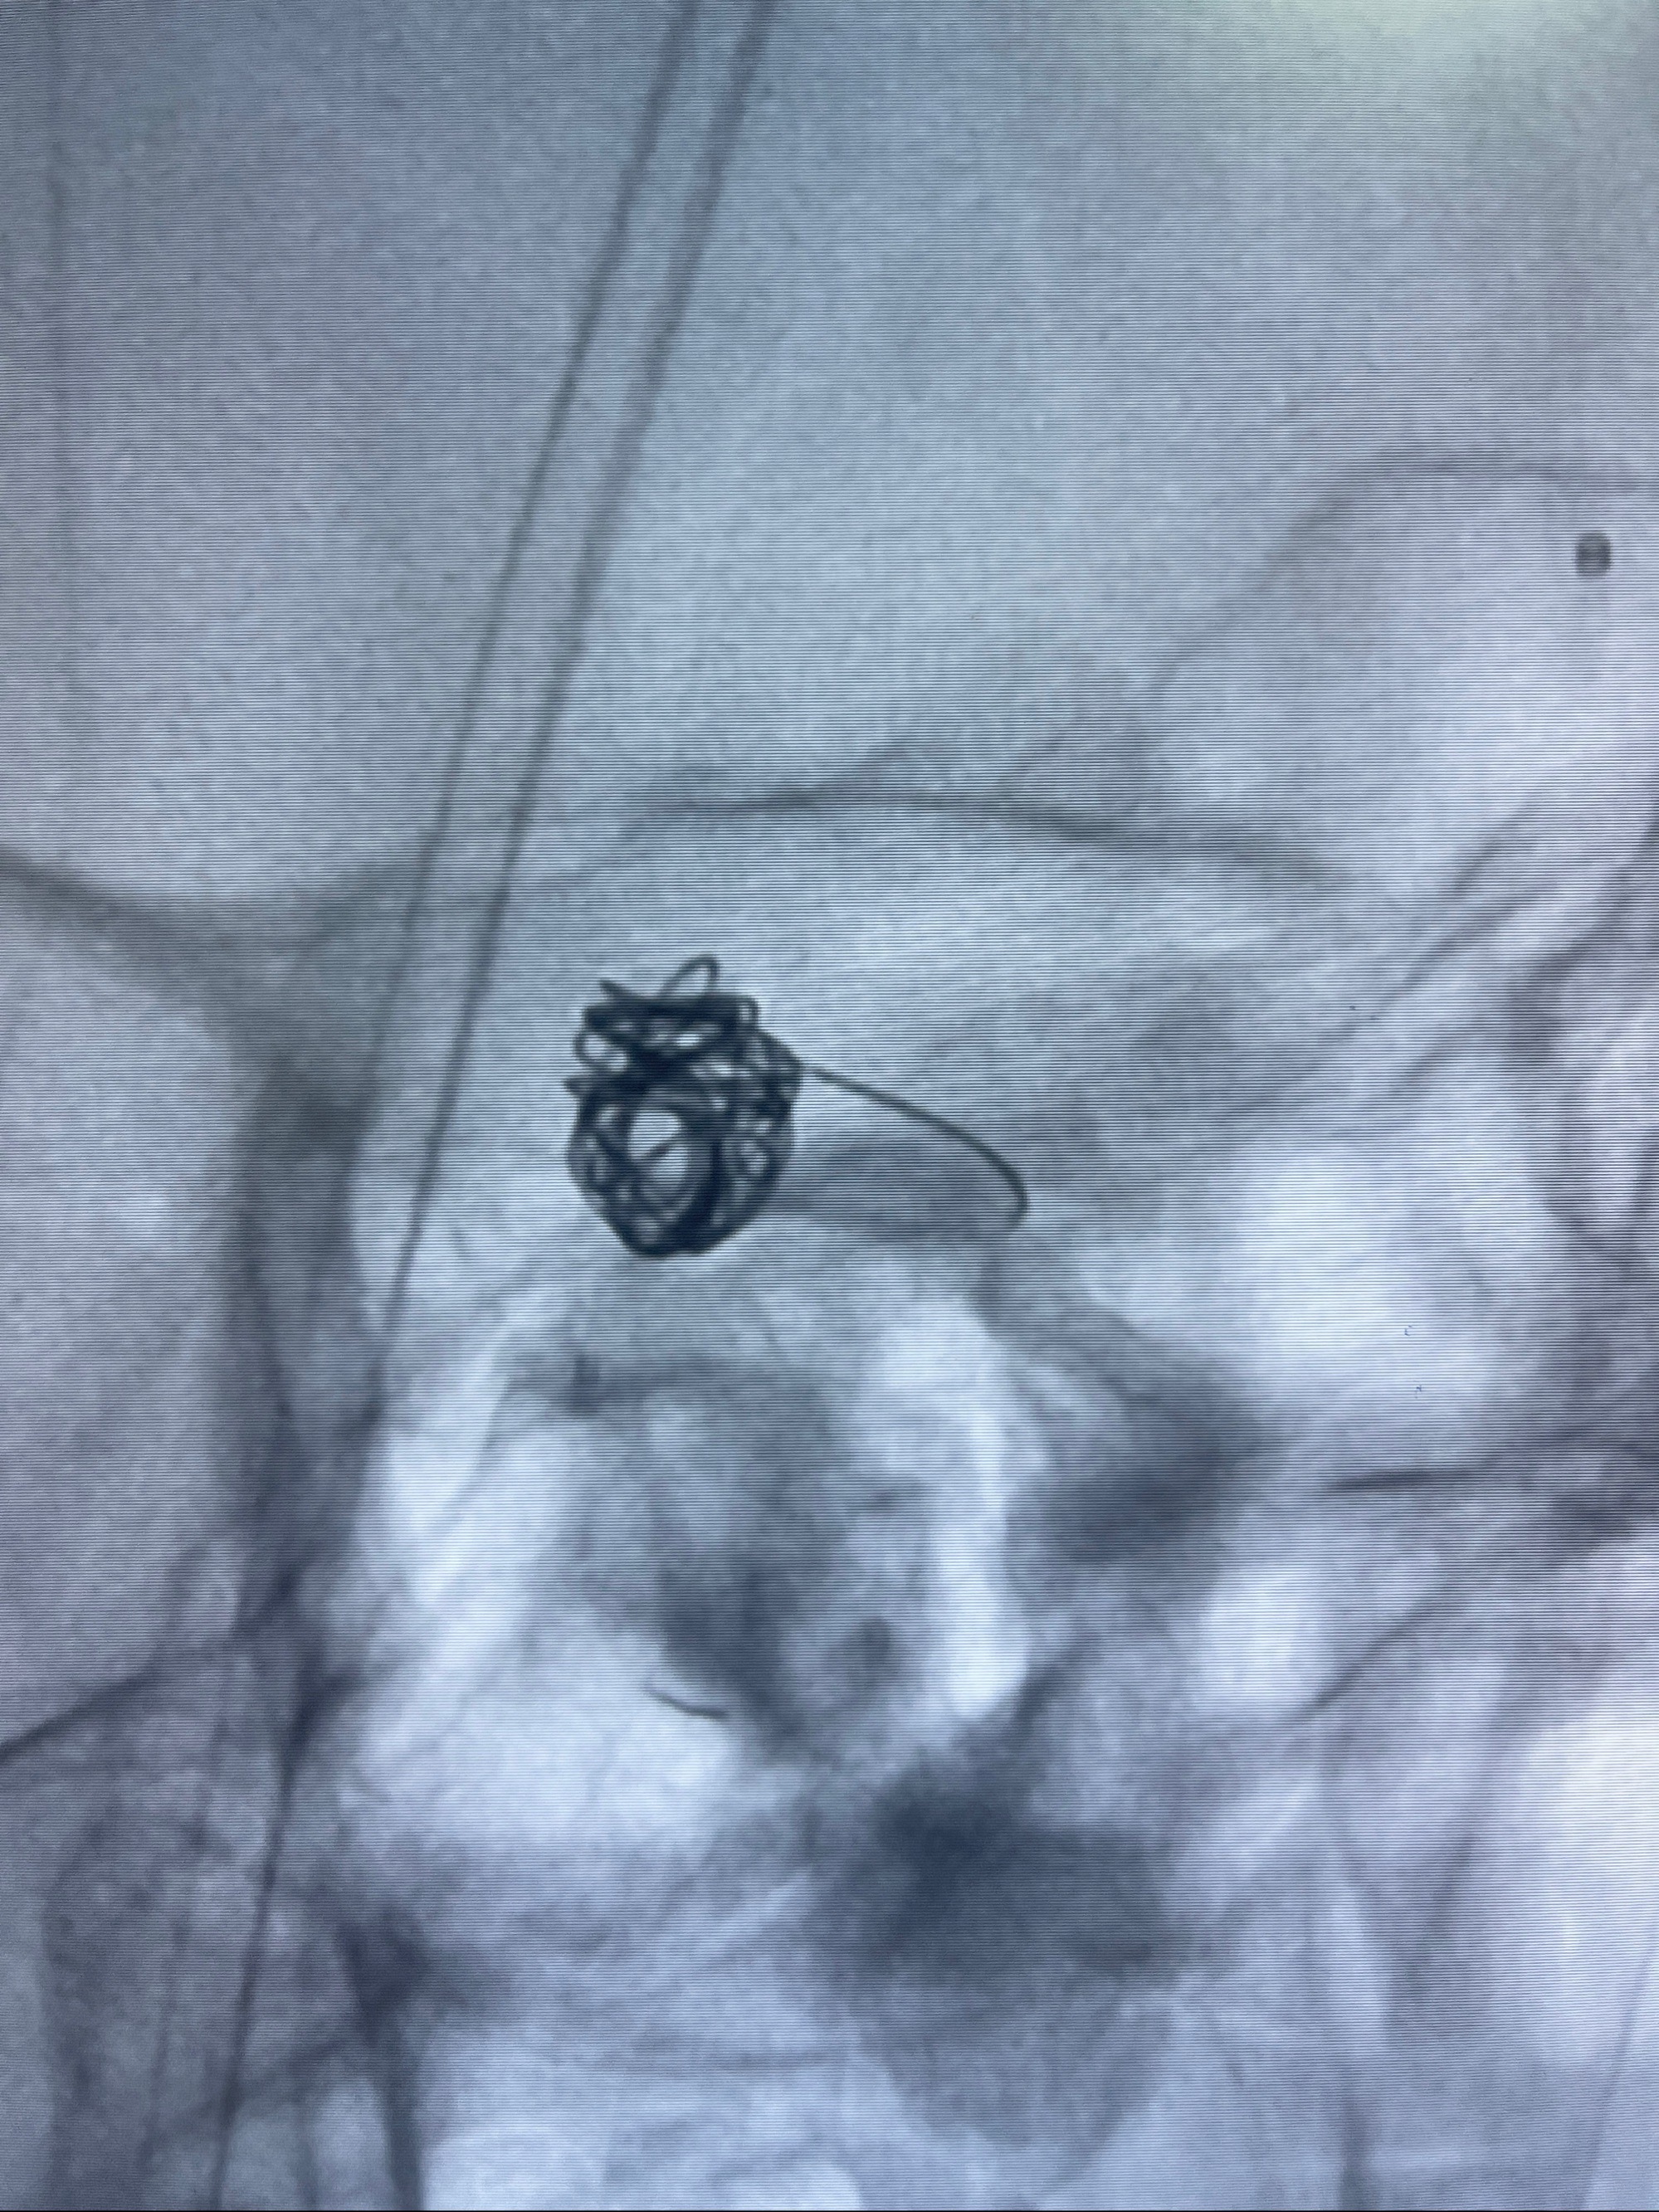

2023-09-06全麻下行左侧颈眼动脉瘤

密网支架辅助栓塞

- Tubridge 4.0-20mm密网支架

- 加奇微弹簧圈:7*30/6*20/5*20/2*8

术后3D显示支架贴壁佳